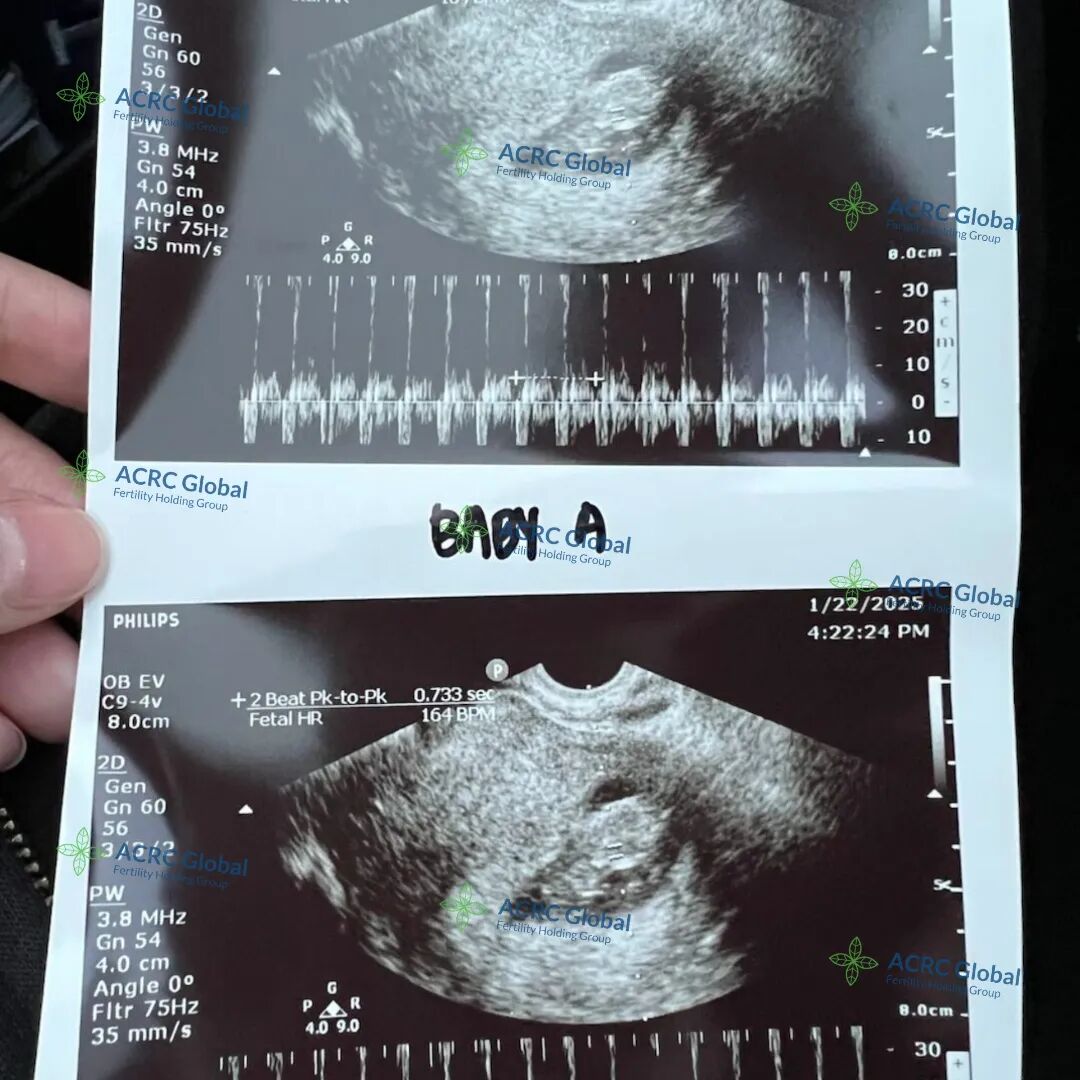

爱妈V的双胎移植也迎来了B超检查,两个宝宝都顺利着床了,宝宝A看起来非常活泼,一直在动,宝宝B则显得格外冷静,两个宝贝性格差异已经初见端倪,实在太有趣了!两位准爸爸听到这个好消息激动不已,已经约定好下一次产检时一同到场,为爱妈加油打气,给予满满支持!